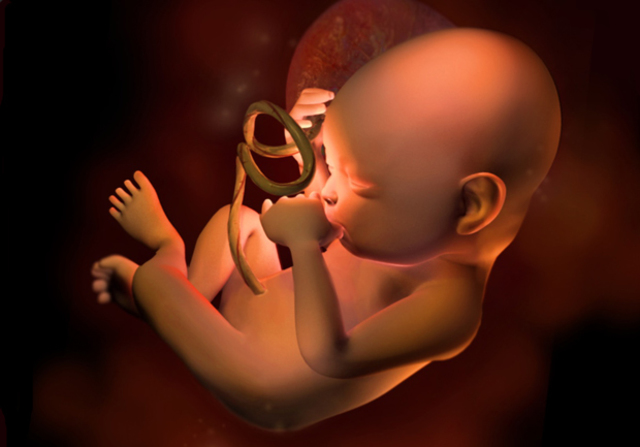

-El cordón umbilical mide 50 cm de largo y 1.3 cm de ancho.

• Semana 40

Semana 40

-Los órganos están maduros.

-El peso promedio es de 3.250g o más

-El feto esta listo para nacer